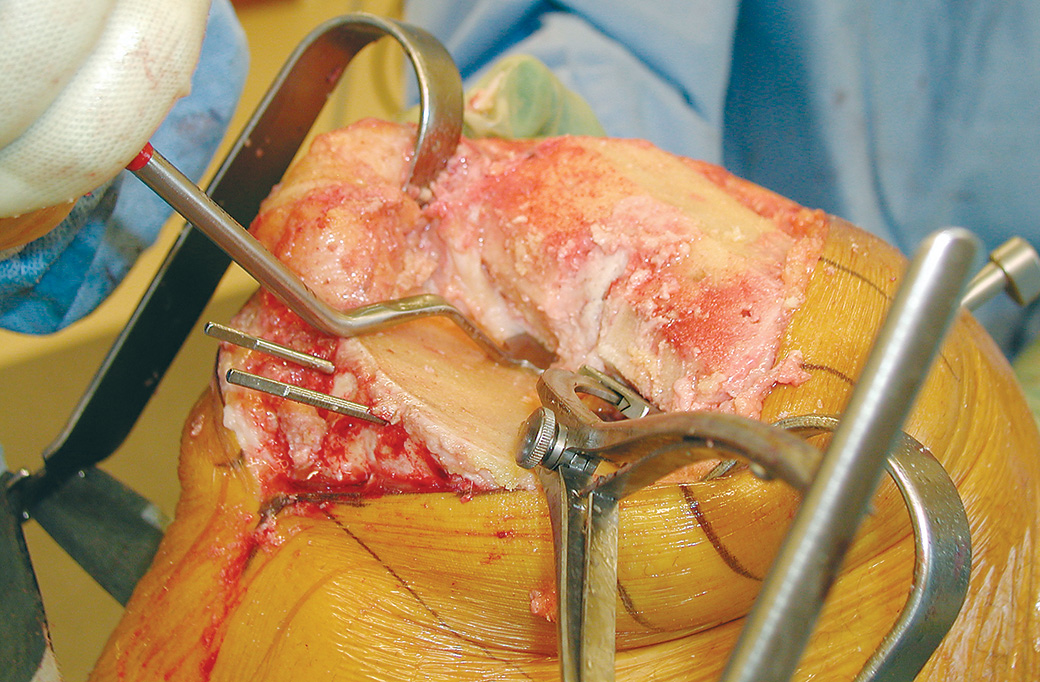

Femoral Tibial Spreader – Medium with Speed Lock and Grooved Pads

Speed lock modification designed by Nasim A. Rana, MD

Helps separate the femur and tibia during total knee replacement surgery

Speed lock helps allow precise control and prevent unintended release.

Designed to remain in position, with the femur and tibia separated, without the need of an assistant, and to minimize crushing the bone, even if osteoporotic. A wide unobstructed view of the posterior compartment is possible. Osteophytes on the posterior condyles of the femur and tibia can be seen and removed.